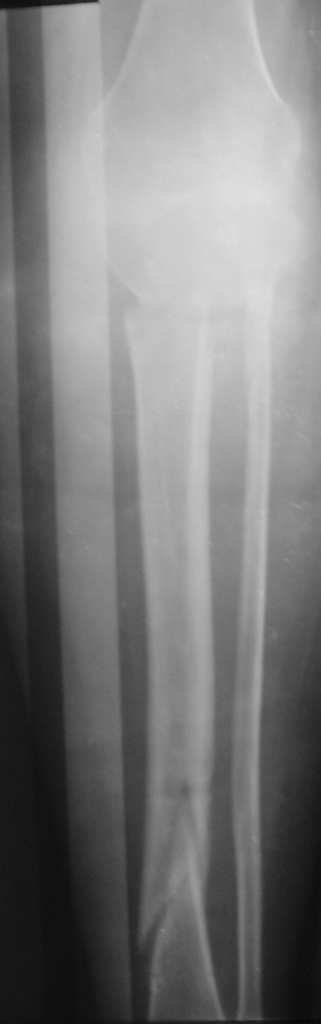

[Ortho] Патологический перелом голени, остеомиелит

Женщина 30 лет,инвалид 1-й группы по рассеяному энцефаломиелиту (клинически нижний парапарез). В январе 2008 года получила закрытый винтообразный перелом большеберцовой кости в н/з и шейки малоберцовой кости со смещением отломков. После травмы развились обширные эпидермальные пузыри голени и голеностопного сустава. После заживления ран произведено наложение аппарата Илизарова.П/о период без особенностей, больная поставлена на ноги (с ходьбой, естественно, проблемы). Наблюдалась на дому. Спустя месяц после операции отмечалось воспаление м/тканей области спиц проксимального базового кольца аппарата, отек в/з голени (больная передвигалась по дому на четвереньках!).Пришлось поменять кольцо на больший диаметр.Воспаление купировали. К концу второго месяца фиксации воспаление в области верхних спиц опять возникло, отделяемое сукровично-гнойное, незначительное.Проводилось местное лечение, отмечался умеренный отек голени в в/з, болезненность, гиперемии не было. Через три месяца после операции - клиническая проба, перелом сросся. Аппарат демонтирован. Спустя 4-5 дней после демонтажа отмечалась гипертермия до 39 в вечернее время. Раны кроме верхних зажили без проблем, верхние - в прежнем состоянии (незначительное серозное отделяемое).Проводилась АБТ, туалет ран, дренирование. Спустя 2 недели после снятия аппарата мать больной отметила появление подвижности в области коленного сустава. При осмотре - деформация голени в в/з (на уровне верхних спиц), подвижность на протяжении в/з, болезненность. Отек умеренный в в/з, гиперемии нет, гипертермия локальная умеренная.Коленный сустав отечен, жидкости нет. Сделали снимки (в приложении) - вот какая картина  Больную госпитализировали - гипсовая лонгета, противовоспалительная терапия, взяли посев из ран. В анализах -лейкоциты до 8 тыс, сдвига формулы нет, СОЭ 42, но больная проходит курсы лечения бетафероном по РЭМ.

Имя     : Сенина-боковая.JPG